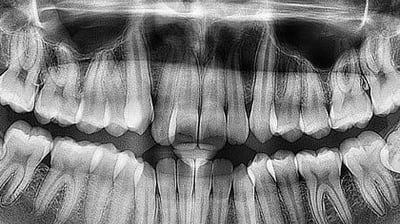

Panoramă dentară

Radiografiile panoramice oferă o imagine completă a întregii cavități bucale, inclusiv a dinților, maxilarelor și articulațiilor temporomandibulare